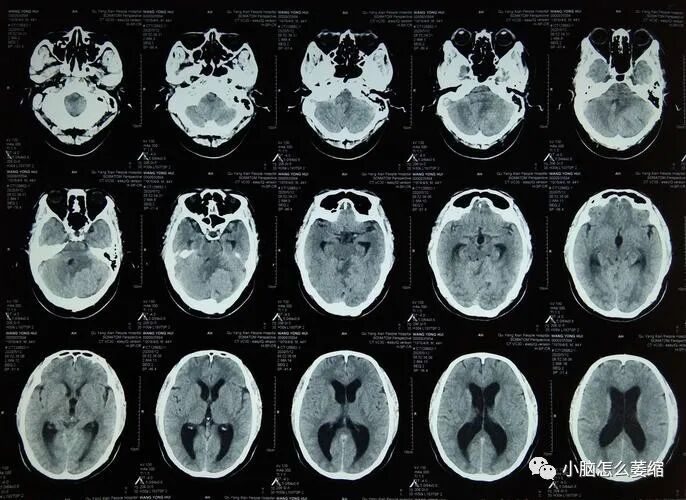

小脑萎缩是一种神经影像学诊断,主要表现为小脑体积缩小,脑沟加深。由于小脑控制着身体的协调和平衡,因此此病通常导致一系列的症状,如步态不稳、语言障碍和动作不协调等。然而,对于小脑萎缩的治疗,往往存在许多挑战,包括药物治疗的局限性。今天,我们分享一个独特的案例,介绍中药在治疗小脑萎缩中的疗效。